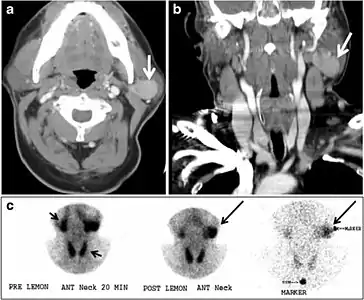

Fig. 18. Lingular thyroid in a 33-year-old male who presented with oropharyngeal bleeding. an Axial enhanced neck CT scan at the level of mandible demonstrates a 3 × 3 × 3.4 cm round, partly well-delineated, heterogeneously enhancing lesion (white arrow). It is predominantly on the left side of the oropharynx and to some extent at the mid part of the base of the tongue. The thyroid gland was normal (not shown). b Image of the anterior face and neck taken 20 minutes after Tc99m-Pertechnetate injection shows absent thyroid radiotracer uptake in normal thyroid anatomical location (black short arrows). There is an area of increased uptake (long black arrows) corresponding to the posterior tongue mass identified on CT scan.[1]

Ectopic thyroid tissue lateral to the orthotopic midline location is rare. The exact anatomical definition of this rare entity is debated in the literature. To avoid confusion, some authors define a lateral neck ectopic thyroid as any thyroid tissue superficial to the strap muscles with no midline continuity. The majority of lateral thyroid ectopia cases have been reported as lesions closely related to the strap muscles. There are few reported cases of ectopic lateral thyroid tissue in the submandibular region, jugulodigastric region, or within the parotid gland substance (Fig. 17).[1]

Fig. 21. Papillary thyroid carcinoma arising from a thyroglossal duct cyst in a 28-year-old male. an Axial enhanced CT scan shows a large complex cystic lesion (white arrows) adherent to the anterior aspect of the hyoid bone. It has an enhancing mural solid nodules and calcifications (black arrows). There is no cervical lymphadenopathy. b Axial short tau inversion recovery (STIR) MRI image near the same level shows complex lesion of high signal intensity (long white arrows) with solid mural nodules (short white arrow). c Axial fat saturated T1 MRI image post contrast administration shows the complex cystic lesion with thick enhancing wall (long white arrows) and enhancing mural nodules (short white arrows).[1]